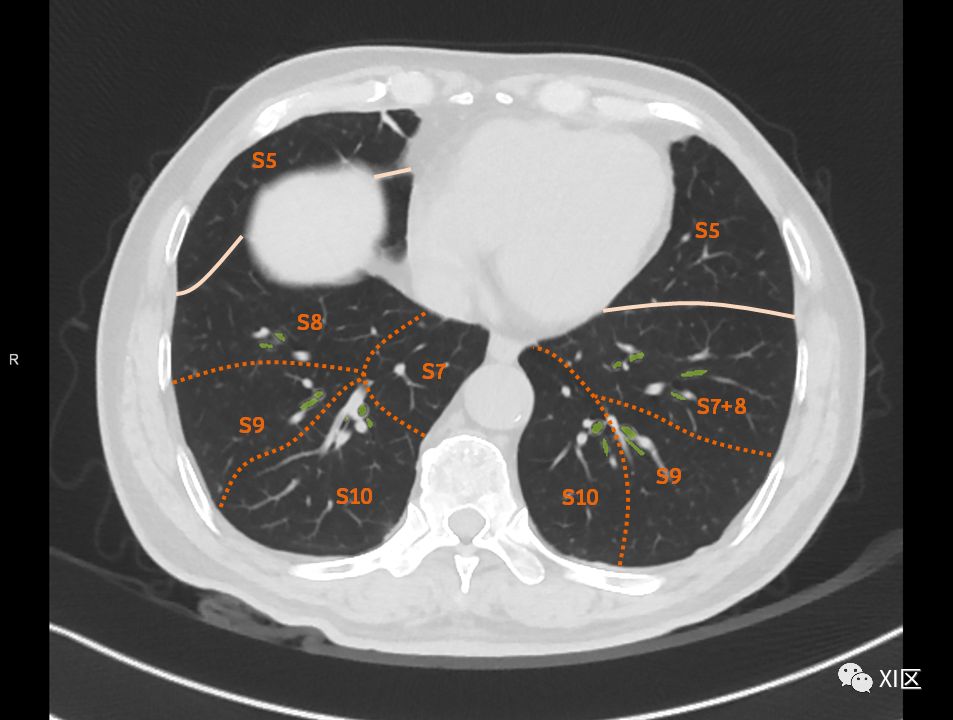

在进行肺的分段时,可以上下观察浏览,沿着相应气管的走形可以更容易准确地进行分段。

肺的断层分段示意图